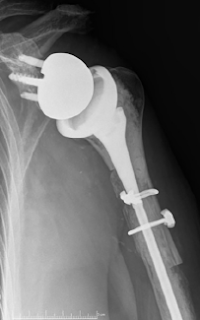

These authors reported their results for 73 patients treated with a reverse shoulder allograft–prosthetic composite (APC) because of proximal humeral deficiency.

If the bone loss was deemed sufficient to compromise the stability of the revision prosthetic stem, then an allograft–prosthetic composite (APC) was chosen to provide enhanced stability of the construct. The fresh-frozen bulk humeral allograft was shaped using an oscillating saw and a step-cut technique. The prepared allograft was then cabled to the host bone using multiple 1.7-mm cables, and the definitive humeral component was cemented into the final construct. The remnant of the allograft subscapularis insertion was used to achieve repair to the remaining native subscapularis with multiple nonabsorbable sutures

Complications occurred in 19 patients (26%). There were 8 periprosthetic fractures, 4 dislocations, 3 patients with humeral loosening, 2 glenosphere dissociations, and 2 infections. In total, 14 patients (19%) required revision. Of the revisions, 6 were for periprosthetic fracture; 2, instability with dislocation; 2, glenosphere dissociation; 2, humeral loosening; and 2, infection. Of the periprosthetic fractures, 3 occurred at the junction of the allograft and host bone and 3 occurred at the level of the distal tip of the humeral stem. Two of the distal fractures presented with radial nerve palsy after the fracture but before revision, and neither recovered at the time of most recent clinical follow-up.

There were 25 shoulders with type I bone loss (< 5 cm), 34 with type II bone loss (5 - 10 cm), and 14 with type III bone loss (> 10 cm). The rate of revision increased dramatically with the amount of bone loss. Revision was performed in 2 shoulders (8%) with type I bone loss versus 7 shoulders (21%) with type II and 5 shoulders (36%) with type III bone loss.

Revision was required in 14 patients (19%) for periprosthetic fracture (n = 6), instability (n = 2), glenosphere dissociation (n = 2), humeral loosening (n = 2), and infection (n = 2) at a mean of 38 months postoperatively. Ten patients had radiographic evidence of humeral loosening at final follow-up.

Comment: This series comes from the practice of a surgeon highly experienced in revision reverse arthroplasty. Surgeons with less experience may not have the same results. Even in these expert hands there was a substantial complication and revision rate, especially in those with massive bone loss.